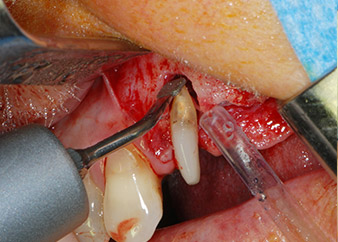

One month later, on the day of surgery, pain and inflammation at tooth 24 were minimal, but mobility of Miller class 2 was still present. After opening the flaps and cleaning the periapical and peri radicular infected tissue, the extent of the bone defect became obvious (Figs. 2 and 3).

At the buccal root, all vestibular and distal bone was missing. Attachment was essentially restricted to the palatal root, underlining the preliminary poor prognosis. Tooth 27 also showed a reduced horizontal attachment and a minimal apical rarefaction (cf. Fig. 1) without clinical symptoms.

total loss of bone and attachment

Fig. 2 and 3: After raising flaps, one month after endodontic revision and initiation of full-mouth periodontal therapy, the buccal root of tooth 24 showed a total loss of bone and attachment.